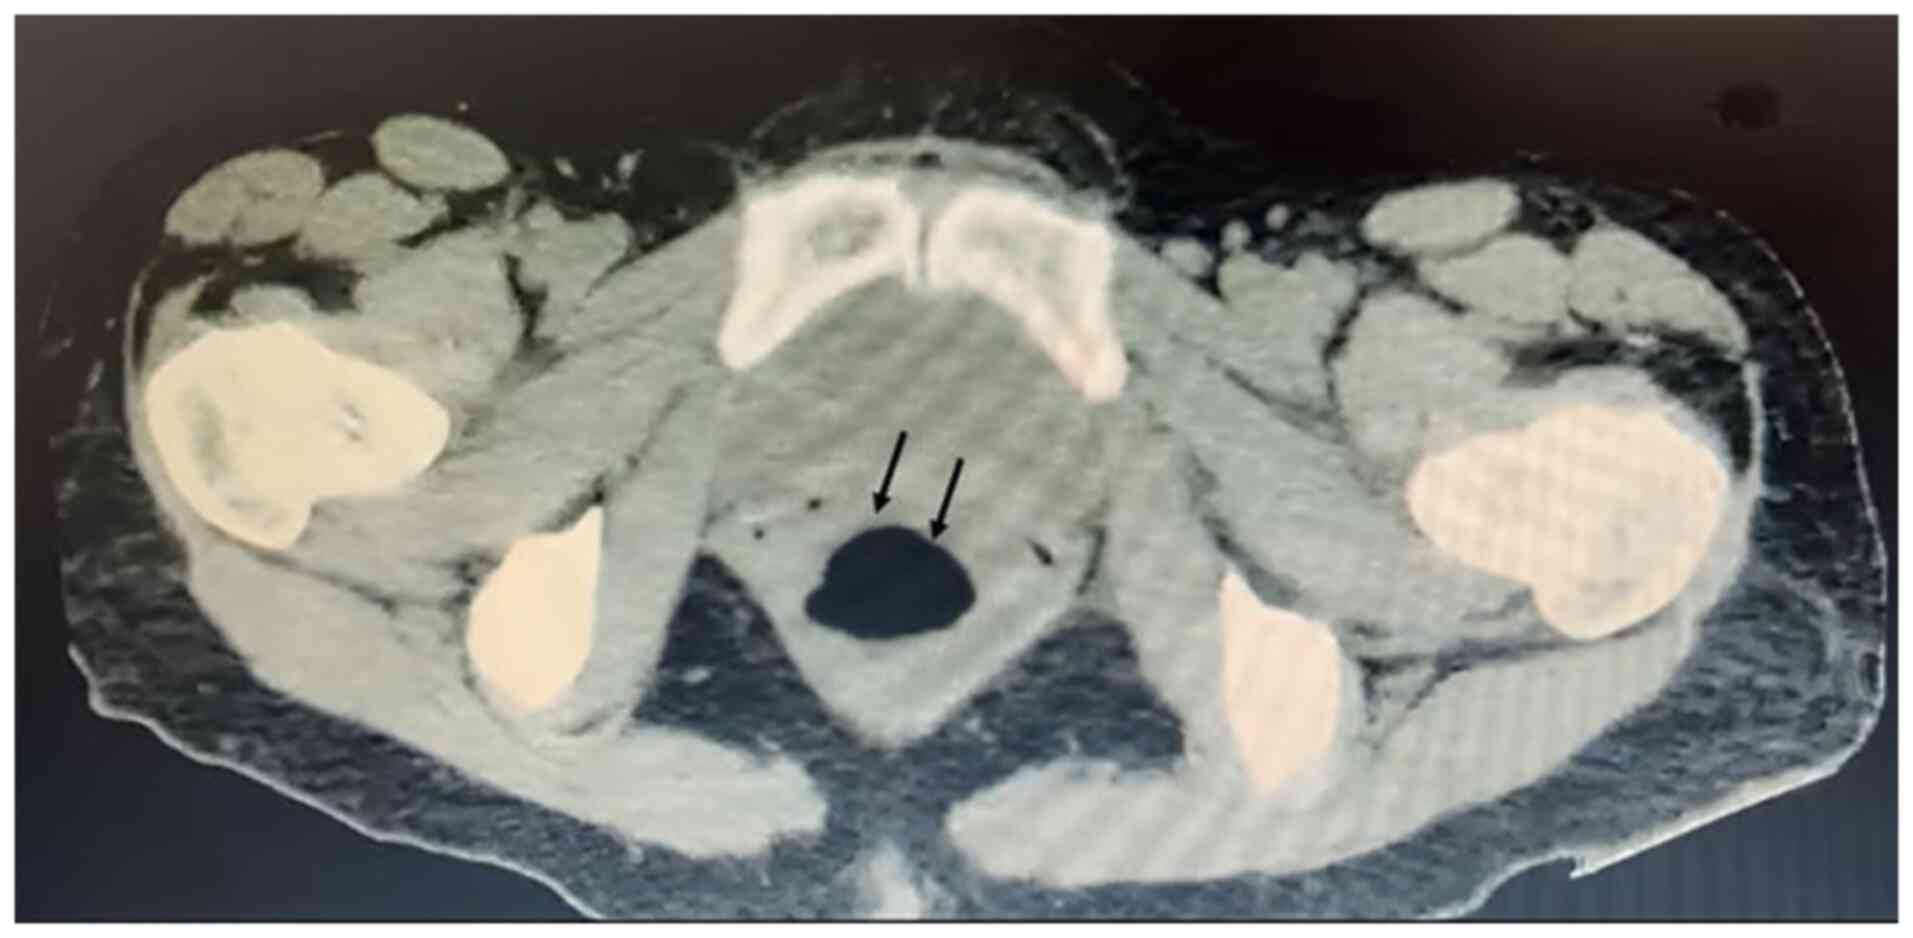

Streptococcus thoraltensis (S. thoraltensis) is a bacterium usually present in the gut microbiome of quadruped mammals. S. thoraltensis is not considered pathogenic for humans; however, several reports have identified it as the etiological agent in cases of chorioamnionitis, postpartum pneumonia and fever of unknown origin. Furthermore, it has been isolated in samples from patients with endocarditis both with and without heart valve replacement. The present study describes the case of a 38‑year‑old healthy female patient who experienced acute abdominal pain accompanied by dysuria, vesical tenesmus and constipation. A computed tomography scan revealed a retro‑uterine cystic mass due to a bacterial abscess. Following surgical drainage, microbiological culture identified S. thoraltensis as the etiological agent. The patient was thus treated with doxycycline and metronidazole, and exhibited a successful response to treatment. The increasing occurrence of S. thoraltensis in human infections suggests potential changes in the epidemiological profile of this bacterium. It is possible that human activity contributes directly or indirectly to the emergence of new pathogens.

Figure 1